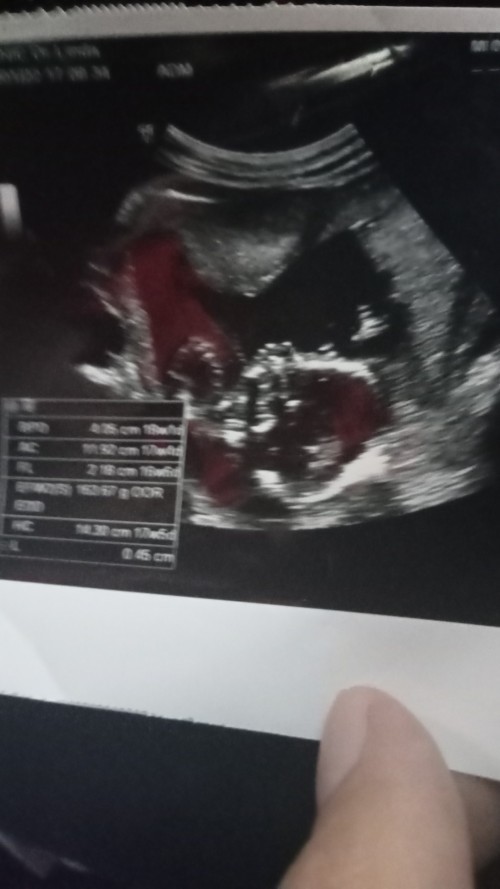

ซาวด์ตอน 19 วีคค่ะ กำหนด 12 มิ.ย